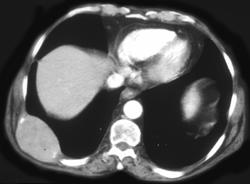

Severe Radiation Gastritis